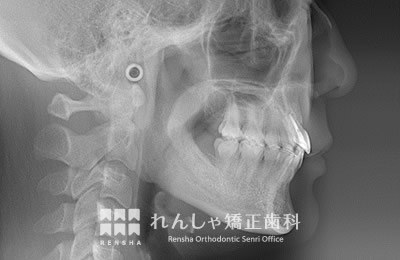

中高生

永久歯列はほぼ完成してしますが、歯列を側方だけでなく後方へも拡大し、埋まっていた右上奥歯を引っ張り出しています。

| 主訴 | 埋まったままでてこない歯がある |

|---|---|

| 診断名 | Angle Class II 小臼歯の埋伏と叢生を伴う上顎前突 |

| 初診時年齢 | 13歳5か月 |

| 装置名 | マルチブラケット装置 |

| 抜歯非抜歯 | 非抜歯 |

| 治療期間 | 2年3か月 |

| 費用の目安 | 約82万円+消費税(検査料金、都度の処置費用等も合わせた総額) |

| リスク副作用 | 歯の移動に伴う軽微な歯根吸収、歯槽骨吸収、歯肉退縮(本症例では軽度の歯根吸収を認めた)、矯正器具装着中のカリエスリスク増大(本症例ではカリエス発生無し) |